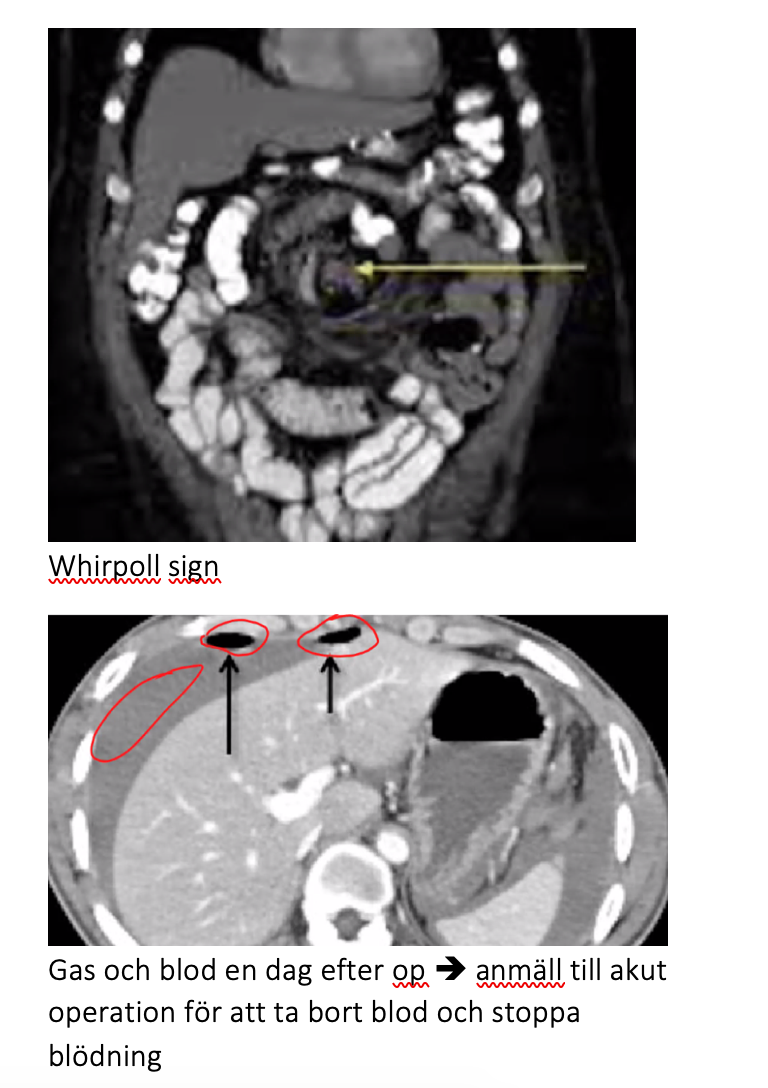

Whirpoll sign

Gas och blod en dag efter op è anmäll till akut operation för att ta bort blod och stoppa blödning